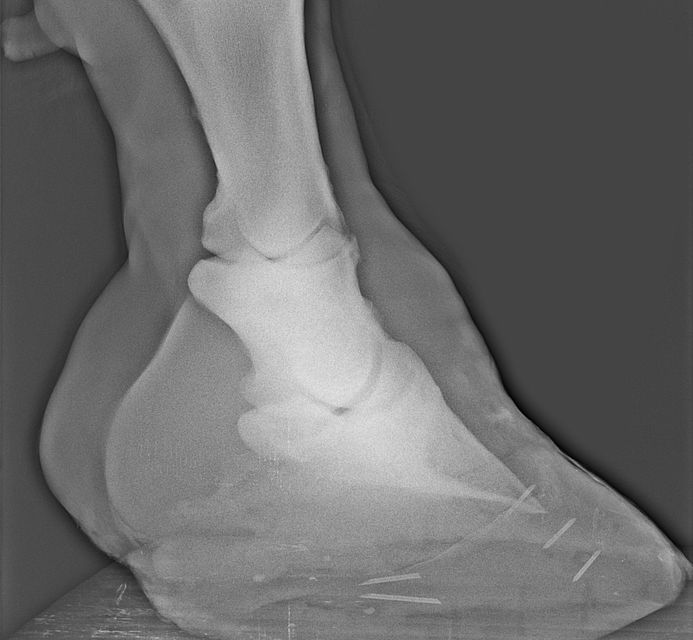

El Hospital cuenta con un servicio de podiatría, dedicado a la clínica del aparato locomotor, cuyas actividades principales incluyen:

El servicio de imaginología incluye los siguientes medios complementarios de diagnóstico: